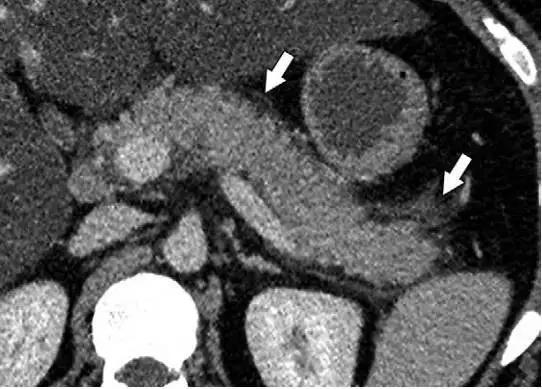

IEP 多表现为胰腺体积局限或弥漫性增大,周围可见条状胰周炎症或少量液性密度(图 1)。

图 1 一名 28 岁男性酗酒引起的 IEP 患者。轴位增强 CT 显示束状胰周炎症(箭头)、胰腺密度正常